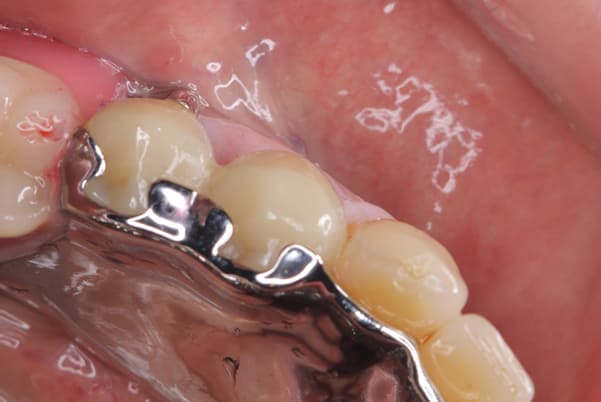

ご自身の歯に負担の少ないバネ、また見た目も改善

ご自身の歯に負担の少ないバネ

銀歯からセラミック歯に

バネをかける歯は繋げることで強度を増し、歯への負担を軽減し、歯の寿命を長くする設計へ。

バネがかかる歯の被せ物は、歯への負担を減らし、入れ歯が動きにくいようになる形態をあらかじめ付与することで、より入れ歯の機能が高まります。

治療を行う際、被せ物や入れ歯は、別々に考えるのではなく、一口腔単位としてお口全体のことを考え最良の治療計画を立てることが歯の寿命、機能効果を向上させるため、専門医としてこのことは常に心掛けて治療を行っています。